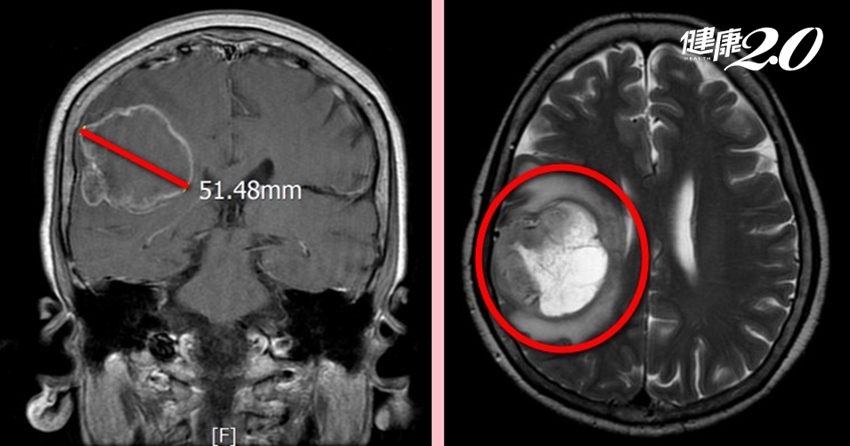

膠質母細胞瘤好發於45歲到70歲,男性罹患率高於女性約1.5倍。郭女士的膠質母細胞瘤屬於第四期,腫瘤大小約5公分,接近腦部大血管。由於膠質母細胞腫瘤的復發率極高,在郭女士術後2周,再給予化學藥物治療,避免復發。

▲由影像學中可清楚看到腫瘤的位置。